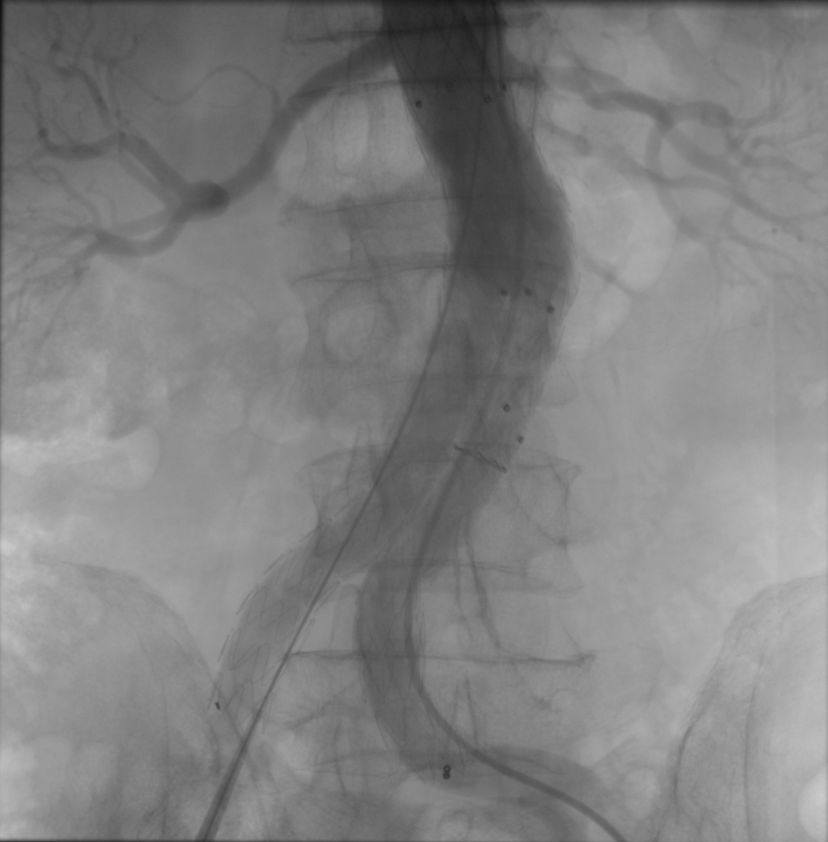

Operasyon, kasık bölgesinden yapılan küçük kesiler aracılığıyla minimal invaziv şekilde gerçekleştirildi. Genişleyen damar bölgesine özel bir greft kaplı stent yerleştirilerek anevrizmanın bulunduğu bölge izole edildi ve damarın normal akışı sağlandı. Bu yöntem sayesinde hastanın iyileşme süresi de açık cerrahiye göre daha hızlı ve konforlu hale geldi.